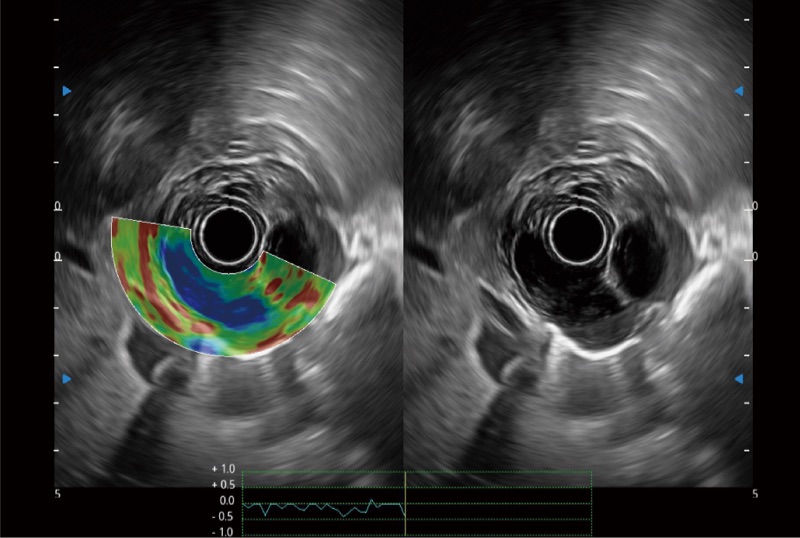

• 伪彩(Chroma)

可人为将灰阶图像转变成彩色的显示方式,增强人眼对于不同回声强度的敏感度,主观上增加了图像分辨率

• 弹性成像

位移矫正技术

不可靠区域自动剔除

弹性定量分析软件